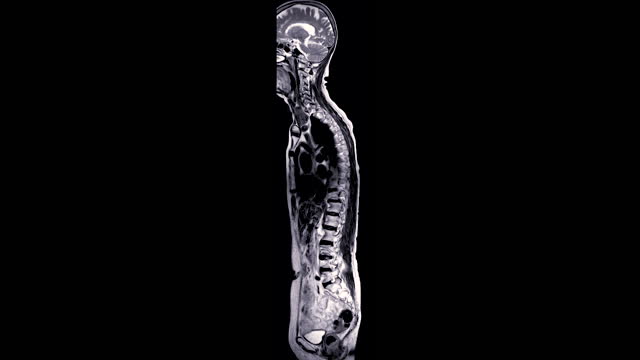

척추관협착증은 척추 주변의 근육과 인대가 퇴행하여 척추관 내 황색 인대가 비정상적으로 부풀어 오르면서 발생하는 퇴행성 척추질환 중 하나입니다. 이 질환은 가까운 거리도 통증으로 인해 걷기가 어려워지는 특징을 가지고 있으며, 새벽에 다리에 통증을 느끼는 경우가 많습니다.